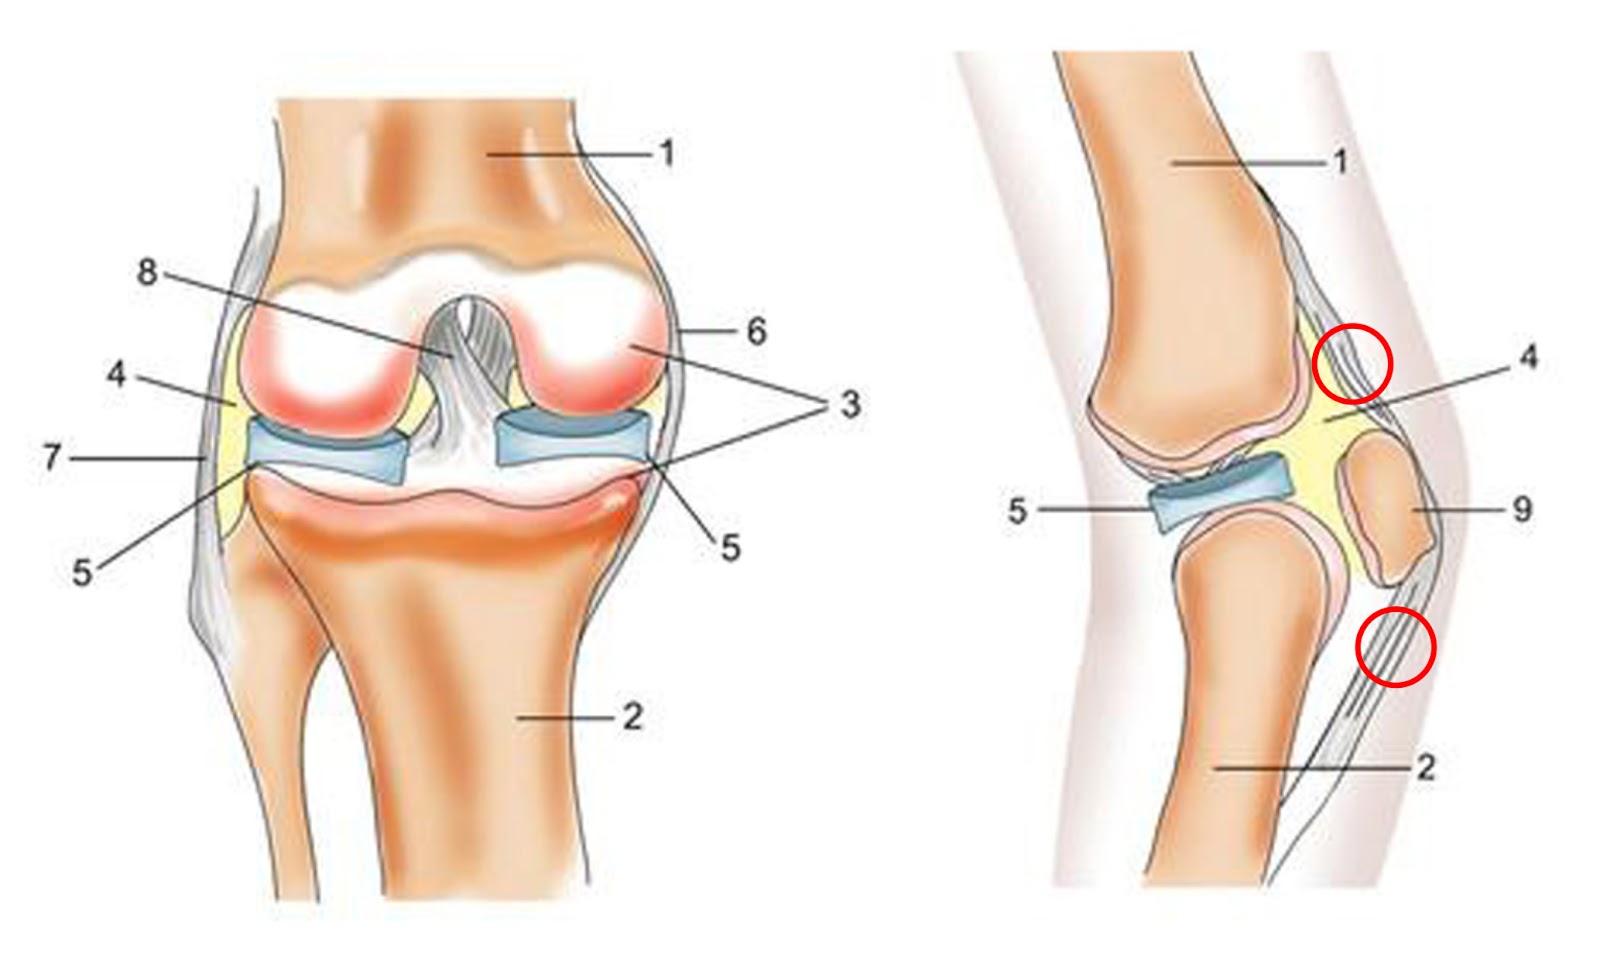

Рисунки Суставов: Анатомические Иллюстрации